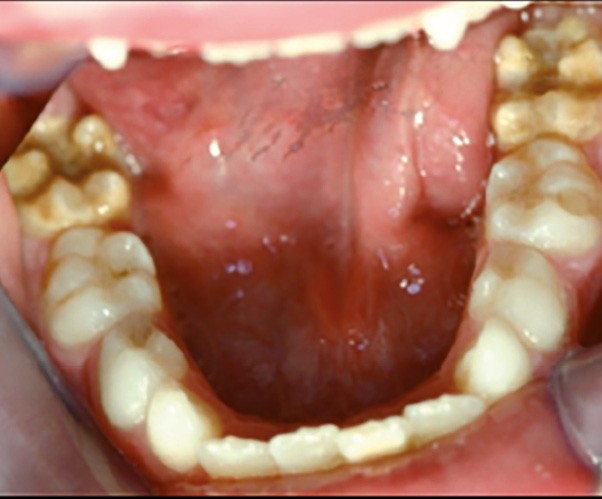

Cliniquement, les dents présentent des colorations blanches ou brunes opaques sur une partie ou sur toute la surface de la dent. Cette atteinte peut être légère (émail blanc, opaque), modérée (coloration jaune, brune, surface crayeuse et effondrement postéruptif de l’email) ou sévère (atteintes associées à des pertes de substances importantes) (fig. 1)

.